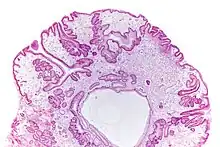

Anatomía patológica

Los pólipos son similares a los del síndrome de poliposis juvenil. Suelen ser sésiles,[2] con dilatación glandular, edema del estroma e inflamación eosinofílica.[4] La tinción para el subtipo de anticuerpo IgG4 es positiva debido a la infiltración de células plasmáticas que lo producen.[5]